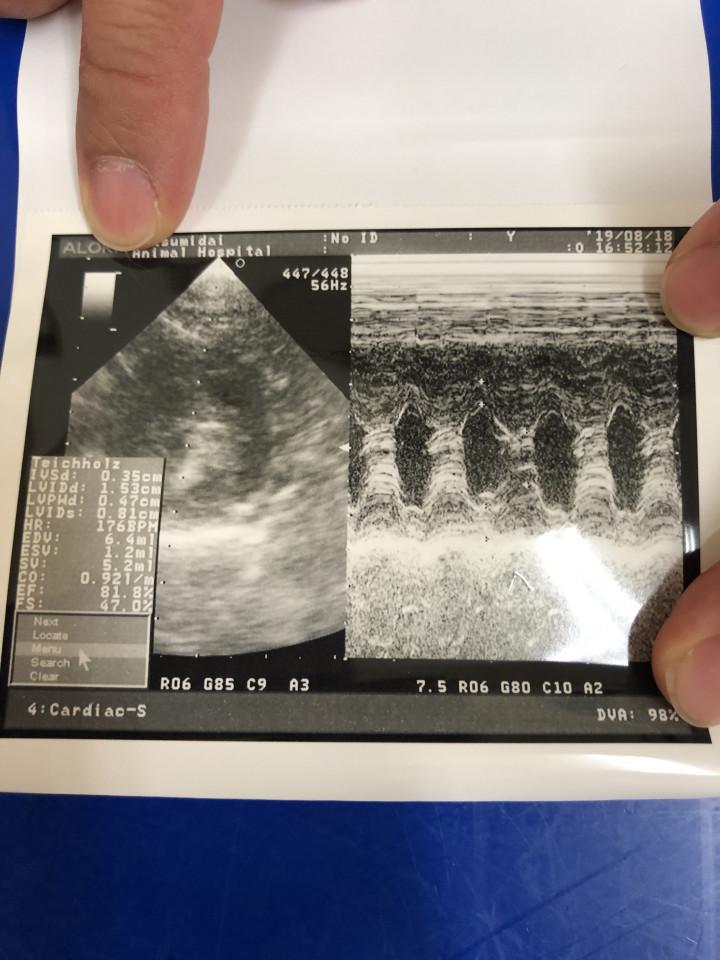

先月、エコー検査して

画像はカルテにもあるはずだろうに

今日も

「 エコー検査をする 」とゆうY先生

1歳時のエコー検査で

心筋壁 6.0mm ・6.9mm

そう、診断されました。

*心電図・レントゲン・ 心臓血液検査は

問題無し

2歳になって

先月の28日のエコー検査では

心筋壁 7.0mm

そして

Y先生による今日のエコー検査では

もなかの心筋壁は

( 認定医の先生が撮ったエコー画像 )

「 3.0mm ・ 4.0mm 」

超音波検査 とゆうのは

獣医師なら誰でも正確に撮れるものでもなく

ちょっとした角度の違いによって

大きく変わりますし

また、精密な診断を求めるには

高性能な超音波検査 機器も重要...